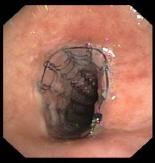

Die Domäne der starren Bronchoskopie ist die Intervention zur Offenhaltung oder Erweiterung der großen Atemwege. Hier setzen wir die Laser-Therapie und Stent-Implantationen ein.

Stent in der Luftröhre |